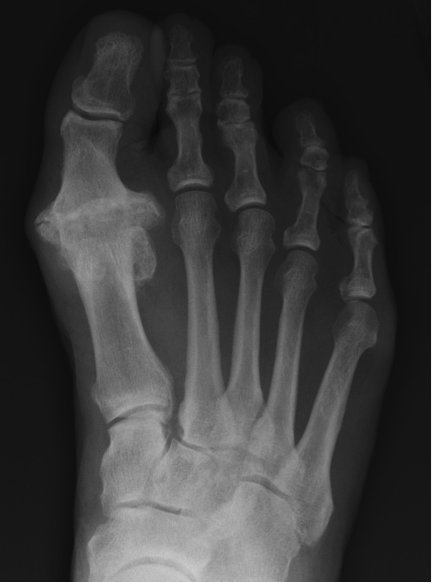

Hallux rigidus is a form of degenerative arthritis that affects the joint at the base of the big toe. It causes pain, stiffness, and limited mobility in the joint - especially during walking or squatting. In its early stages, the condition is referred to as hallux limitus, where the range of motion is reduced but not completely lost. As the condition progresses and the joint becomes increasingly stiff and immobile, it is classified as hallux rigidus. Because bone spurs can form around the joint, it is sometimes mistaken for a bunion.

Hallux rigidus is essentially osteoarthritis of the big toe joint. It may develop due to abnormal foot mechanics, repetitive stress, or direct trauma to the joint. Structural factors - such as a long first metatarsal bone or an existing bunion deformity - can also increase the risk. Over time, these issues lead to the breakdown of cartilage within the joint, resulting in pain and stiffness.

Patients may experience pain at the top of the big toe joint, swelling, difficulty bending the toe, and trouble with everyday activities like walking uphill or squatting. In colder weather, symptoms may worsen. In severe cases, patients may walk with a limp to compensate for the stiffness. Early diagnosis is key to effective management. Your foot specialist will examine the joint, review your medical history, and order X-rays to assess the extent of joint damage. Identifying the condition in its early stages allows for more conservative and effective treatment options.